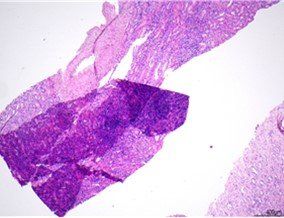

ਐੱਚ ਐਂਡ ਈ - ਬੀਐਮਟੀ ਸਕੀਮ

ਇਹ BMT ਬਾਇਓਪਸੀ ਦੀ ਇੱਕ ਸ਼ਾਨਦਾਰ ਤਿਆਰੀ ਹੈ, ਜਿਸ ਵਿੱਚ ਸੰਤੁਲਿਤ H&E ਸਟੇਨਿੰਗ, ਵਧੀਆ ਕ੍ਰੋਮੈਟਿਨ ਵੇਰਵੇ, ਅਤੇ ਬੋਨ ਮੈਰੋ ਟਿਸ਼ੂ ਦੇ ਅੰਦਰ ਸੈੱਲ ਕਿਸਮਾਂ ਦੇ ਚੋਣਵੇਂ ਸਟੇਨਿੰਗ ਹਨ। ਇਸ ਸਲਾਈਡ ਨੂੰ ਮੁਲਾਂਕਣ 'ਤੇ 9/10 ਸਕੋਰ ਕੀਤਾ ਗਿਆ ਸੀ।